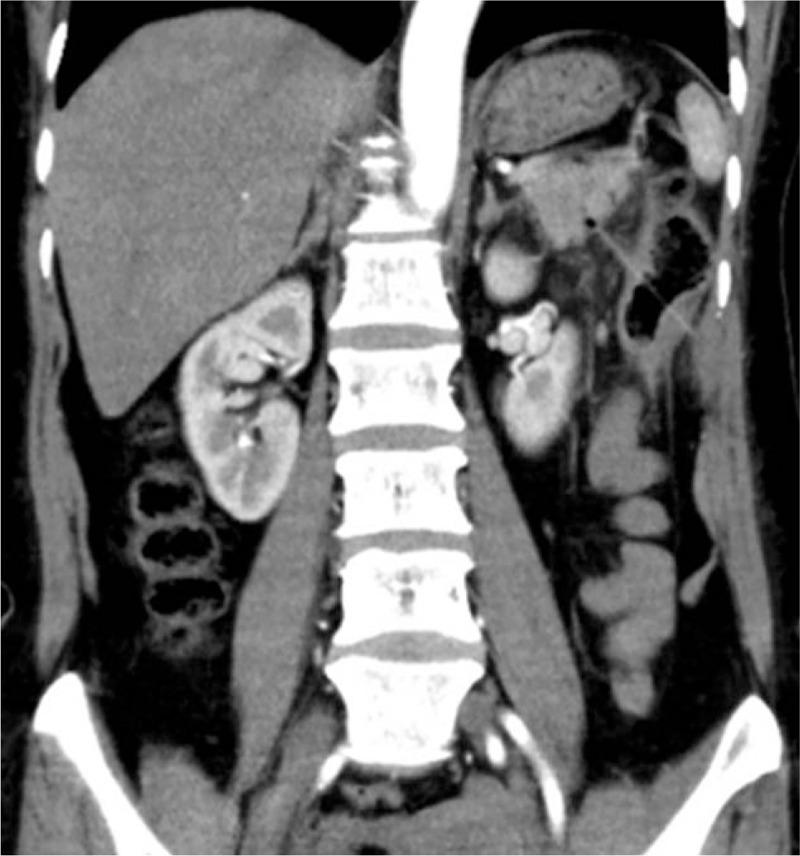

No serious problem was discovered in the examination and blood test. There were somewhere abnormal in computed tomography (CT) images and ultrasound (US). Then a toothpick was found penetrating the wall of intestine into the adjacent viscera in the laparotomy.

When accepting patients with abdominal pain, suitable examining means and careful observation should be given to find easily ignored lesions. CT is recommended in the diagnostic process of swallowed foreign mass. When there is a vague place, US can be used for further diagnose.

检查和血液检测未发现严重问题。计算机断层扫描(CT)图像和超声(US)检查有异常。随后在剖腹手术中发现一根牙签穿透肠壁进入相邻脏器。

接诊腹痛患者时,应采用合适的检查手段并仔细观察,以发现易被忽视的病变。在诊断吞咽异物时建议使用CT。当有不明确之处时,可使用超声进一步诊断。